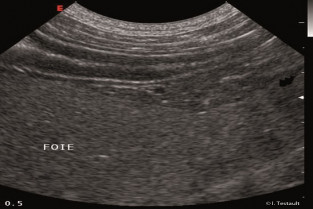

Echographie des affections parenchymateuses hépatiques

Cours

Guillaume Gory